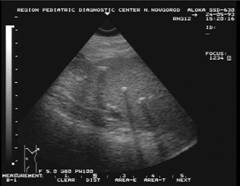

Splenomegalie la un pacient cu

malarie in antecedente